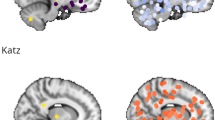

Resting state networks (RSNs) presenting between-groups significant clusters of increased functional connectivity in PCC respect HC, obtained from dual regression analyses (p < 0.05, corrected for multiple comparisons). Maximum coordinates based on Montreal Neurological Institute (MNI) space are indicated. The right hemisphere is displayed on the left side of axial and coronal views. Abbreviations: HC, healthy controls; IC, independent components; PCC, post-COVID condition.

We identified 47 meaningful RSNs among the 50 components extracted by ICA from the whole sample. The PCC group showed increased intra-network FC compared with the control group in 10 RSNs (Fig. 1 and Supplementary Table 5), including the default mode network (DMN), executive control network (ECN) and salience network (SN), auditory network (AUN), superior parietal lobule, anterior cingulate cortex, and basal ganglia network (BGN) (p < 0.05, corrected for multiple comparisons).